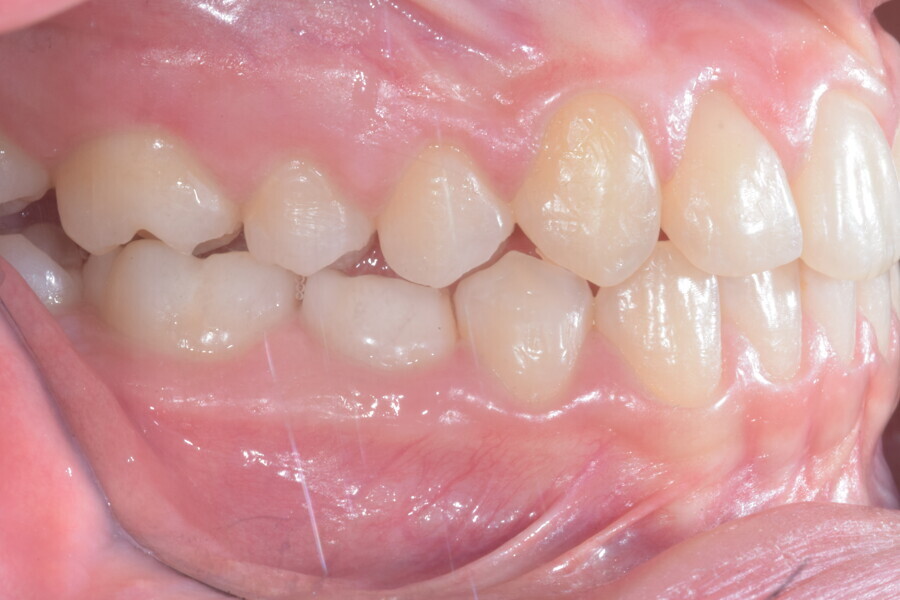

A 14-year-old female patient presented with the chief complaint of midline deviation and dental crowding in both arches. Facial analysis showed a hypodivergent growth pattern, a normal nasolabial angle, a harmonious profile and proper chin projection. Clinical examination revealed a Class III skeletal relationship (ANB = 0°) and Class I molar relationship. The maxillary right canine was absent, and this had led to space loss and mesial drift of posterior teeth on the right side, resulting in a slight Class II molar relationship. The maxillary left canine had erupted in a high position. The mandibular arch displayed crowding despite the agenesis of the right second premolar and the persistence of the primary molar (Figs. 3–11). The radiograph showed the probably premature loss of the maxillary right primary canine and consequently impacted maxillary right permanent canine, and the agenesis of the mandibular right second premolar and the mandibular right third molar (Fig. 12).

Fig. 3